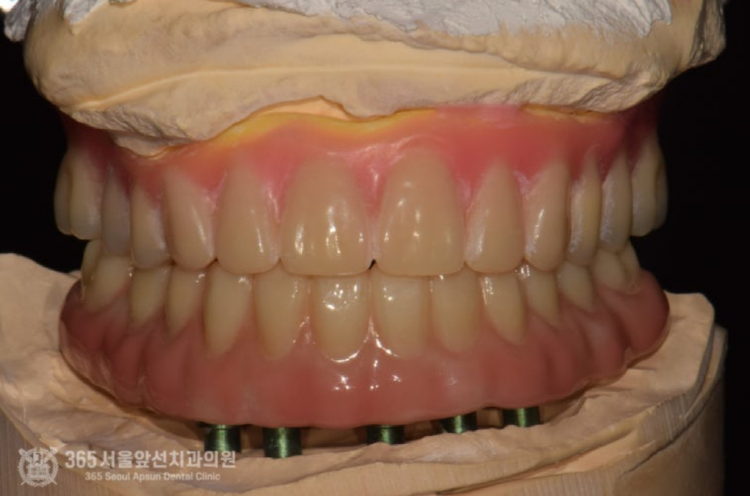

위 사진은 All on X라는 보철물 내부에 들어가는 금속구조물입니다. 정확한 용어로는 Mesostructure라고 합니다. (다른 환자분 케이스에서 사용된 금속구조물이지만 이해를 돕기위해 참고용으로 넣었습니다) All on X 보철물의 특징상, 단단한 강도가 매우 중요하며 보철물의 적합성이 매우 중요합니다. 따라서 정교한 작업이 필요하며 다소 번거롭더라도 여러번의 작업이 필요합니다. 촬영일시 : 2025.01.02. 아래쪽 보철물은 All on X 라고 하여 메탈 바가 들어가는 복잡한 방식의 보철물이기에 정확도가 생명입니다. 따라서 번거롭더라도 석고 모형 상에서 한번 맞춰보는 작업도 필요하기에 진행하였습니다. 위턱에 식립한 임플란트가 단단하게 굳었을때 쯤 임플란트에 치유지대주라는 단추를 연결합니다. 이제 슬슬 본을 떠도 되겠습니다. 양측 어금니 부위에 뼈가 매우 부족하여 상악동 거상술을 진행하였던 부위도 뼈가 생성되는게 관찰됩니다. 아래턱 보철물이 입안에 위치된 상태입니다. 아래만 맞춰봤는데 환자분은 벌써부터 기대감이 대단하십니다. 이 단계쯤되면 저도 두근두근합니다ㅎㅎ 위아래 보철물이 모두 장착된 상태에서의 파노라마 엑스레이 사진입니다. 제가 치료해드렸지만 제가 봐도 만족스럽습니다 ㅎㅎ 촬영일시 : 2025.01.15. 촬영일시 : 2025.01.15. 위아래 보철물이 모두 들어간 상태의 구강내 사진입니다. 환자분은 치료가 끝나고 눈물을 글썽글썽하셨습니다. 전체 임플란트 치료는 그만큼 요구되는 수준이 높고 의사도 힘들고 환자분들께서도 힘들지만 치료가 마무리 되고 나면 기억에 많이 남는것같습니다. 오늘도 매우 뼈가 좋지 않았던 환자분의 고난이도 치료 증례를 소개해드렸습니다. 앞으로도 좋은 치료 증례로 도움이 될 수 있게 노력하겠습니다. 지금까지 365일 열린 가까운 서울대학교 치과병원을 지향하는 주안동치과 365서울앞선치과였습니다. 감사합니다. [ 치료기간: 2024년 7월3일 ~ 2025년 1월 15일 ] ※ 365서울앞선치과의원의 모든 포스팅은 각 진료과 의료진이 직접 작성합니다. 365서울앞선치과의원 블로그의 임상 케이스 게시물은 환자분께 의학적으로 정확하고 상세한 정보를 드리기 위해 각 진료과 의료진이 직접 작성하며, 모든 증례 사진은 본원 의료진이 직접 시술한 증례를 촬영한 것으로, 의료법 제23조, 제56조에 의거하며 환자분의 동의를 얻어 포스팅에 사용하였습니다. 또한 해당 케이스는 본 환자분의 치료 결과이며, 환자 상태에 따라 치료의 결과는 달라질 수 있습니다. |